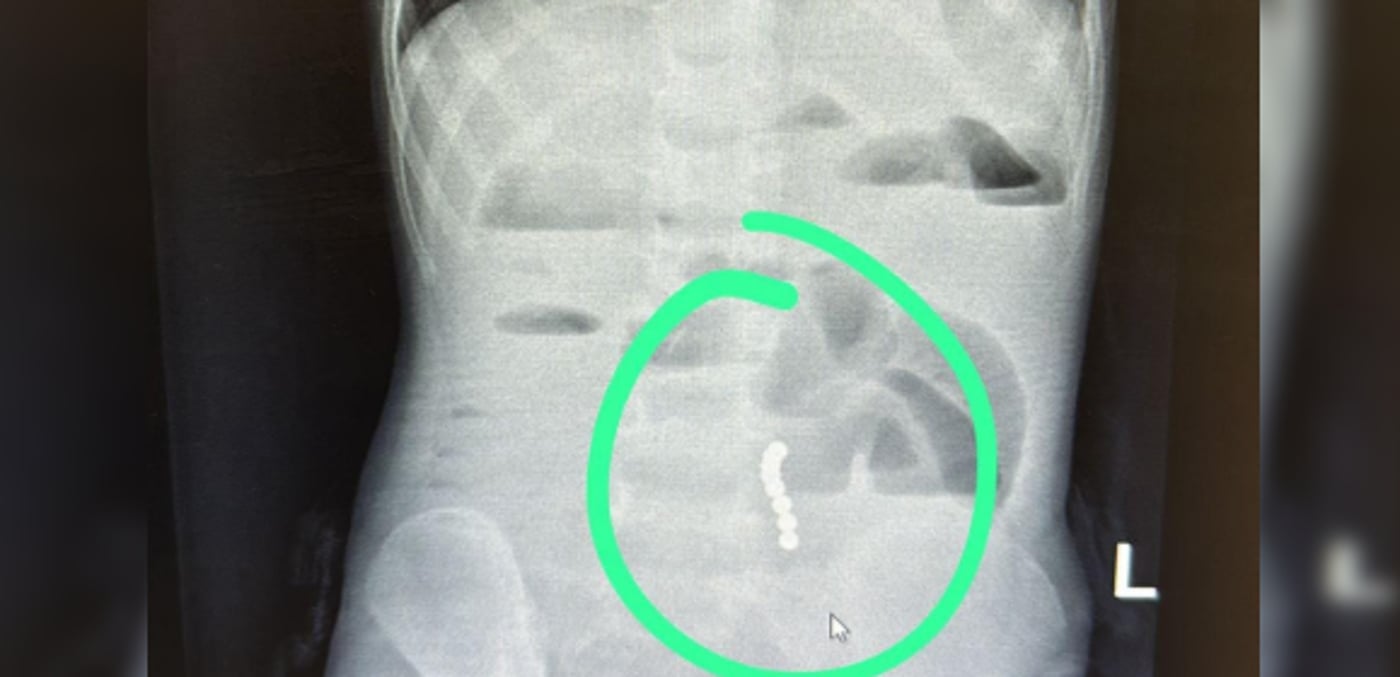

ד”ר ליאת יניב, רופאה בכירה במחלקת ילדים במרכז הרפואי בני ציון, זיהתה ממצא שעורר חשד לבעיה משמעותית במערכת העיכול. בצילום הדמיה שבוצע בדחיפות, הודגמו מגנטים במעי הדק עם עדות לחסימת מעי.

בהתייעצות עם ד"ר ראוף נאסר, מומחה גסטרו ילדים, הפעוט הופנה להמשך טיפול כירורגי ונותח באופן דחוף ע"י ד”ר דניאל דובין, סגן מנהלת מחלקת כירורגיית ילדים במרכז הרפואי בני ציון ו ד"ר יאיר בן שמואל, רופא בכיר בכירורגיית ילדים, כאשר ד"ר אבו ראס עומר היה הרופא המרדים הבכיר. בניתוח הוצאו שמונה כדורי מגנט מהמעי הדק.